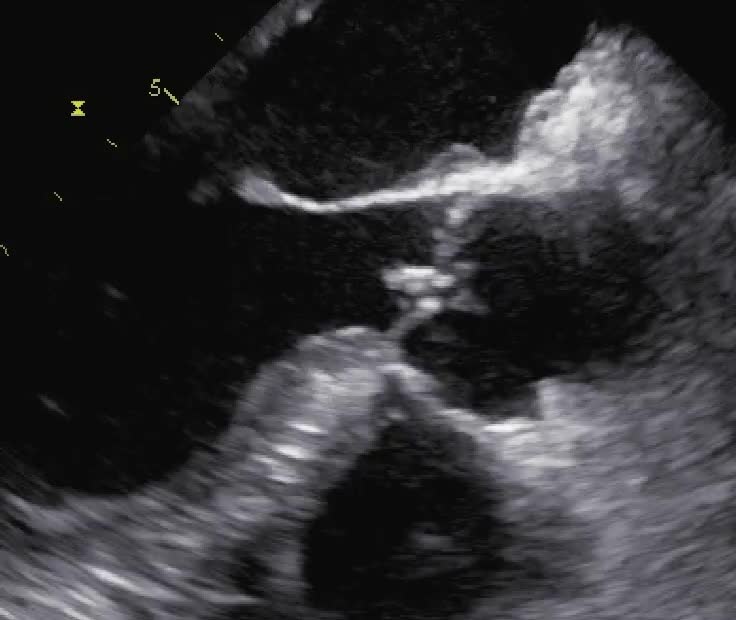

Distacco di protesi meccanica mitralica da endocardite infettiva con severo rigurgito paraprotesico

Autore:

Manfredo Cerchiello